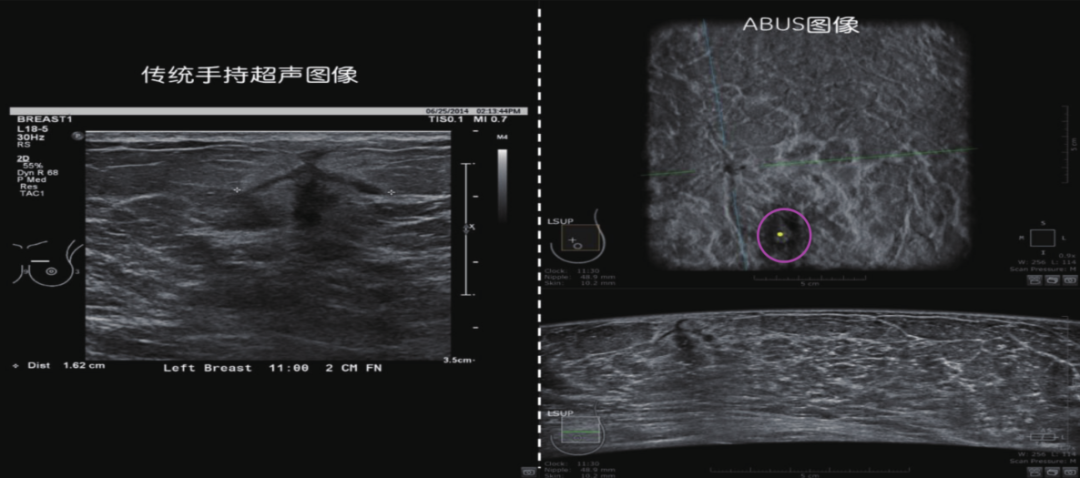

乳腺肿瘤超声